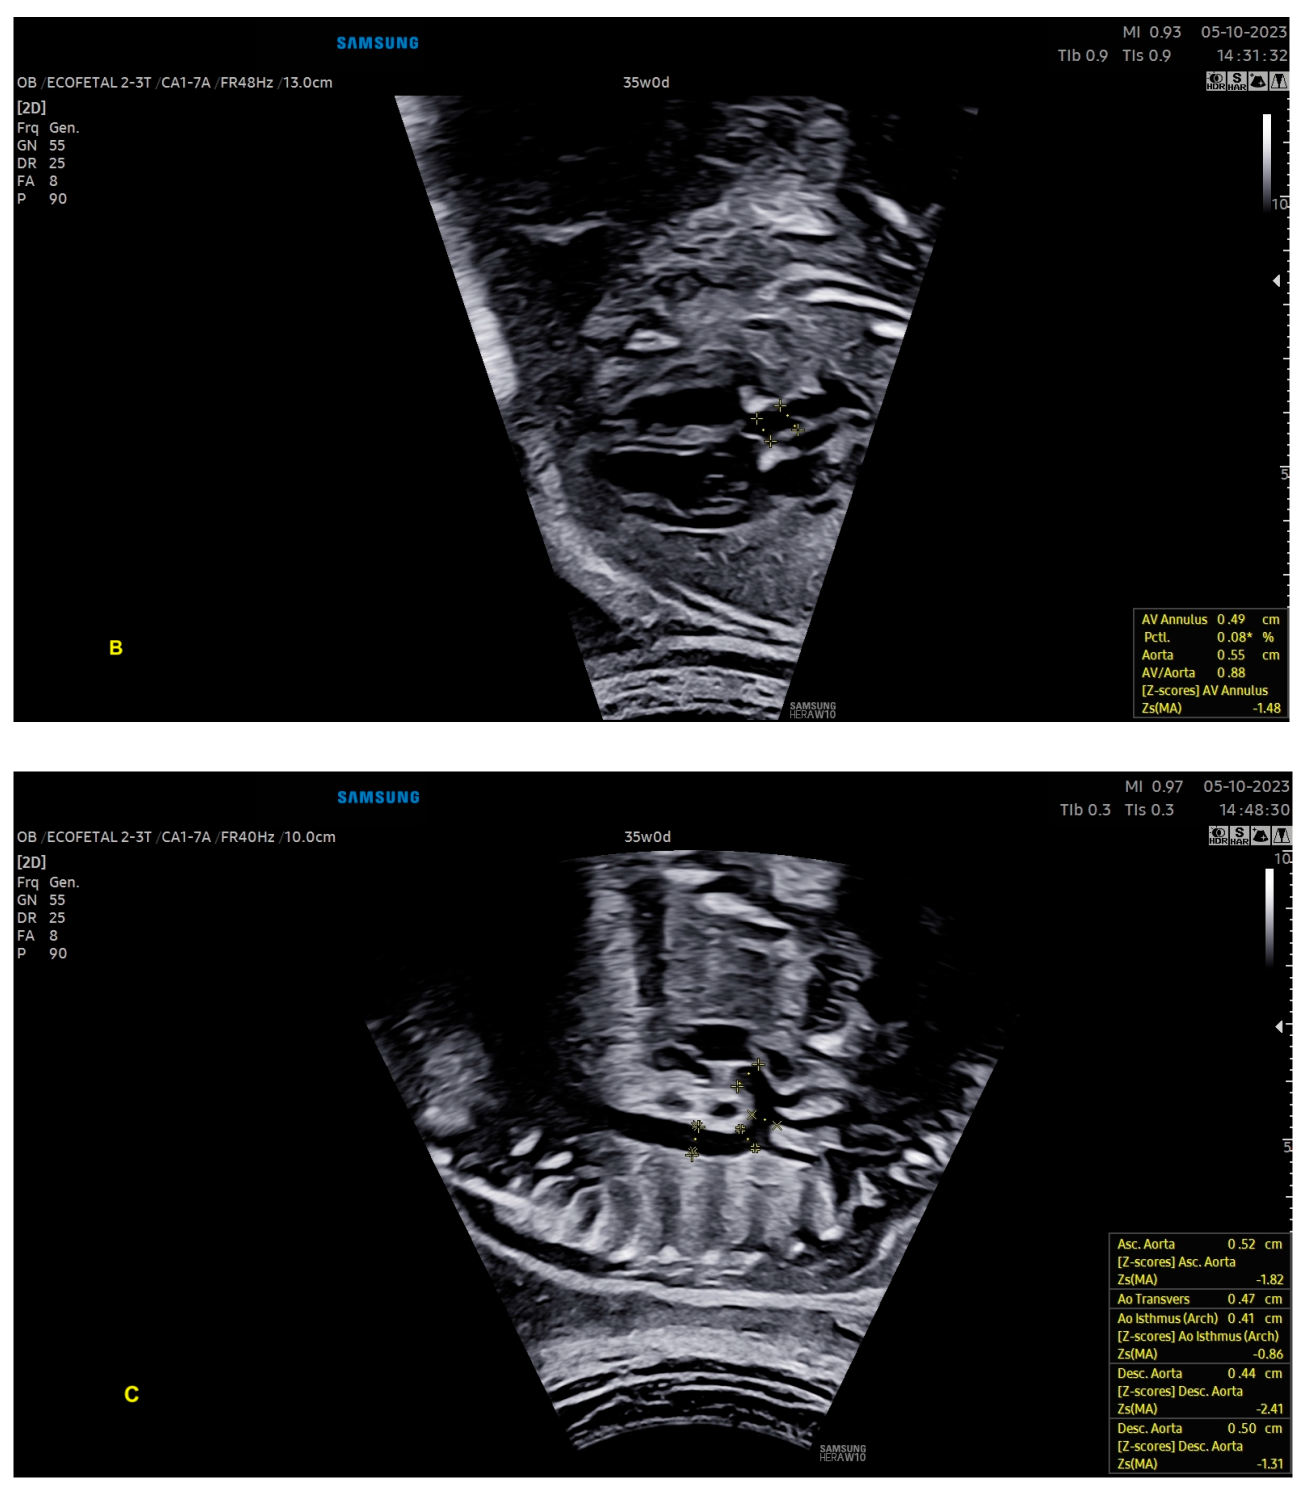

- Scharf, J.L.; Dracopoulos, C.; Gembicki, M.; Welp, A.; Weichert, J. How Automated Techniques Ease Functional Assessment of the Fetal Heart: Applicability of MPI+™ for Direct Quantification of the Modified Myocardial Performance Index. Diagnostics 2023, 13, 1705. [Google Scholar] [CrossRef] [PubMed]